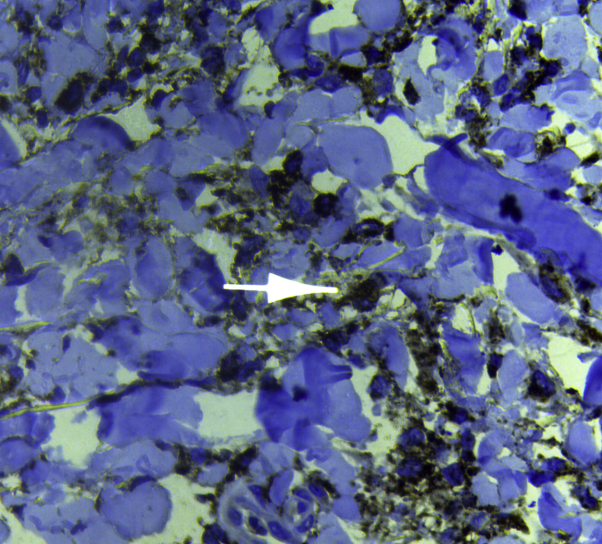

Fig 5.

A biopsy from the hyperpigmented patches of patient 3 shows orthokeratosis, acanthosis, and basal-layer hyperpigmentation, in addition to widespread fibrosis and thickened collagen bundles with mononuclear cell infiltrates in the dermis. (Hematoxylin-eosin stain.)

This patient was previously described by the authors,6 but that additional clinical information is reported herein. A 17-year-old Iraqi boy, the son of consanguineous healthy parents, presented to our outpatient clinic with hyperpigmented indurated patches with overlying hypertrichosis involving the inner aspects of the thighs, calves, and ankles (Fig 3) associated with bilateral ankle swelling and pain, hallux valgus, and flexion deformities in the toes (Fig 4) and little fingers. Severe deafness was evident, and the patient communicated by using sign language. He also had gynecomastia, musculoskeletal pain, corneal arcus, exophthalmos, bilateral optic disc swelling, premature graying of the hair, hypospadias, short stature (see Table I), and inguinal lymphadenopathy. According to the parents, the older brother of this patient has bilateral swelling of the feet and deformities of the toes but without skin lesions. A biopsy from the hyperpigmented patches found orthokeratosis, acanthosis, and basal-layer hyperpigmentation in addition to widespread fibrosis and thickened collagen bundles with mononuclear cell infiltrates in the dermis (Fig 5). Immunohistochemistry showed diffuse infiltration of CD68+ histiocytes in the dermis (Fig 6). An abdominal ultrasound examination found mild hepatosplenomegaly, and a DXA scan found low BMD (Z-score, −2.6). Brain magnetic resonance imaging was normal. For a summary of the clinical and laboratory findings, see Tables I and II.